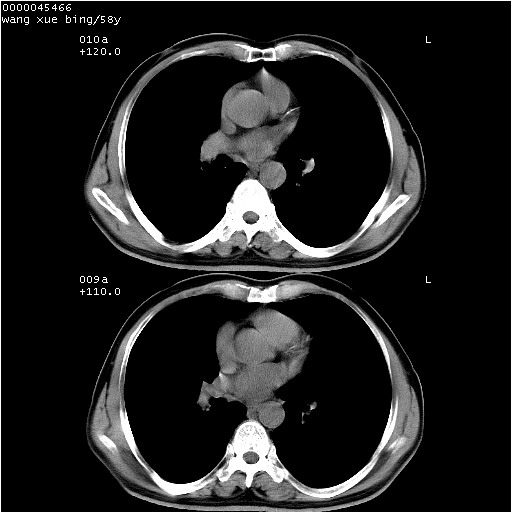

患者 男,58岁。咳嗽、咯血3月余。

胸部ct轴位平扫(层厚10mm,螺距1.5,重建间隔10mm),图像如下:

右肺下叶团块及不规则空洞,内壁不规则,外缘见粗长毛刺,临近胸膜明显增厚并与病灶关系密切。支持考虑:右肺肺脓肿!建议穿刺病理检查待除外周围型肺癌!

考虑右下肺中心型肺癌并远端阻塞性炎症及胸膜及纵隔淋巴转移

右肺下叶周围型肺癌伴空洞形成!征象比较明显!分叶、毛刺、胸膜凹陷征、厚壁空洞,壁结节!

影像符合癌性空洞表现,临床如无咳大量浓臭痰史,还是考虑周围型肺癌可能性大。

空洞壁厚,不规则,其内可见壁结节,周围可见毛刺及阻塞性炎变,多考虑癌性病变.